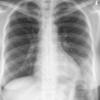

Case 2 Lingular pneum PA

Date: 04/17/2005

Views: 5942